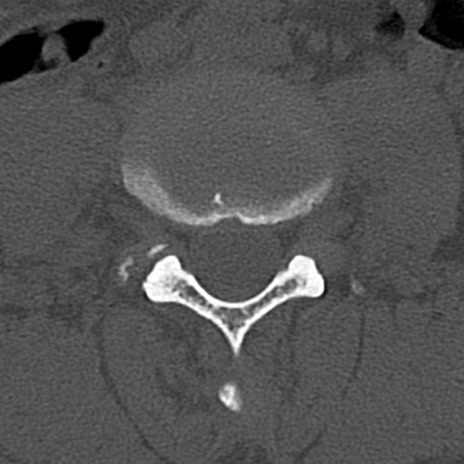

腰椎CT

横断像と矢状断像